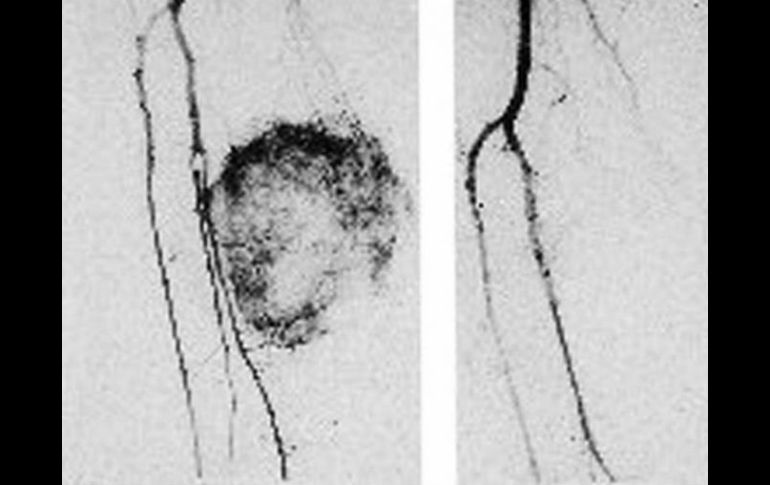

Suplementos | Una nueva técnica quirúrgica permitirá salvar extremidades Evitan amputación por cáncer Una nueva técnica quirúrgica permitirá salvar extremidades de pacientes con sarcomas en tejido blando Por: EL INFORMADOR 30 de marzo de 2014 - 03:26 hs En México, los sarcomas de tejidos blandos se presentan en más de dos mil adultos cada año. ARCHIVO / GUADALAJARA, JALISCO (30/MAR/2014).- La amputación de brazos y piernas en adultos con cáncer de tejidos blandos (sarcomas), no era una opción. Sin embargo, con el propósito de evitar esa cirugía, es que el Hospital México Americano ha recibido la certificación para realizar una nueva técnica que extirpe el tumor sin poner en riesgo la extremidad. De acuerdo con el doctor Roberto Larios Casillas, Cirujano Oncólogo de esta institución con sede en Guadalajara y quien fuera el responsable de uno de estos procedimientos quirúrgicos, en nuestro país los sarcomas de tejidos blandos se presentan en más de dos mil adultos cada año, y se localizan en las extremidades en 60% de los casos. Otras áreas del cuerpo que son afectadas se encuentran en el tórax, abdomen, cabeza y cuello. Uno de los problemas “es que el sarcoma en fases muy tempranas presenta síntomas inciertos”, comenta el especialista. Dada la formación de una protuberancia alrededor del brazo o la pierna, los afectados generalmente llegan al hospital hasta que el tumor se encuentra en fase avanzada, siendo la amputación la única vía para combaritlo. Perfusión Aislada de Extremidad (PAE) Denominada como Perfusión Aislada de Extremidad (PAE), “es una cirugía que permite retrasar o evitar la pérdida de un brazo o pierna, aún cuando el tumor se encuentra en etapa avanzada o no se puede quitar sin el riesgo de dañar estructuras vitales. Sin embargo, dicho procedimiento sólo es posible realizarlo de manera segura en hospitales que cuenten con infraestructura suficiente y adecuada”, comentó el doctor Casillas. El paciente que fue tratado en el Hospital Mexico Americano es un hombre de 60 años de edad, con sarcoma en la pierna derecha en la que el procedimiento permitió hacerla independiente al resto del cuerpo. Es decir, mediante una bomba de circulación extracorpórea se aplicó un agente biotecnológico conocido como “Factor de Necrosis Tumoral”, así como una dosis de quimioterapia, lo que permitió reducir dicho tumor y facilitar la extracción. ¿Cuál es el impacto en las personas que son tratadas con la PAE? El doctor Casillas comenta que “el impacto es positivo, ya que estamos ante un procedimiento que evita la incapacidad física y muerte prematura de cientos de personas a escala nacional, lo que además les permite ser económica y socialmente activos”. Sin embargo, este tipo de cirugía no es nueva, ya que desde 2010 viene expandiéndose en México a través de una decena de hospitales de tercer nivel, como el México Americano, siendo recientemente certificado y transformándose en un sitio clave en el Occidente del país para este tipo de intervenciones. De esta forma, los jaliscienses cuentan con esta alternativa en el tratamiento de una de las variantes del cáncer. Temas Cáncer Pasaporte Salud general Lee También ¿Cómo otros países han reducido el tabaquismo? Estas son las vacunas recomendadas en época de frío ¿Por qué duelen las manos cuando hace frío? Estos son los riesgos de tener una vida sedentaria Recibe las últimas noticias en tu e-mail Todo lo que necesitas saber para comenzar tu día Registrarse implica aceptar los Términos y Condiciones